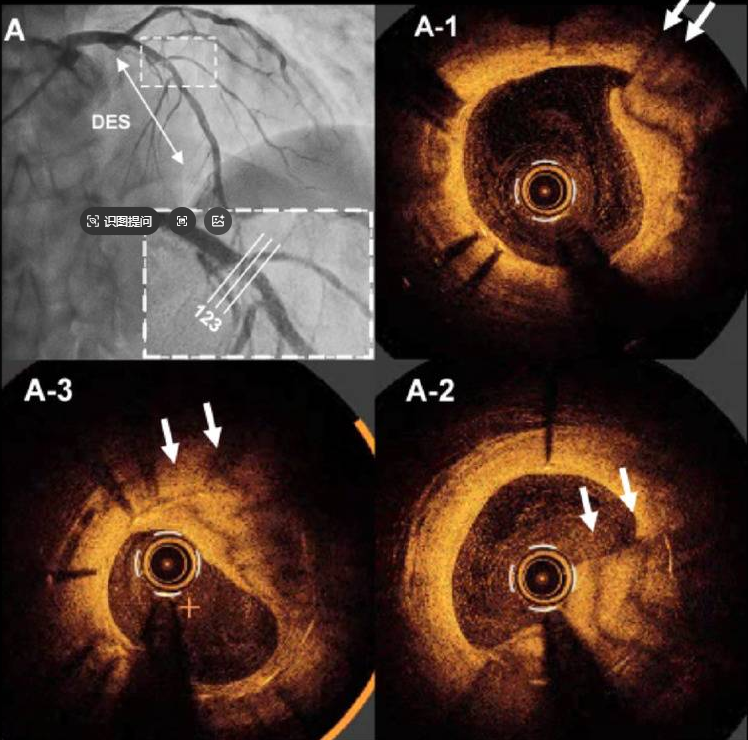

OCT显示,一个呈条纹状、低衰减的斑块,从支架梁的外侧突入至管腔内。(图A1-3;视频1)

A 冠状动脉造影显示LAD中段有模糊病变。A1-3 OCT图像显示条纹状、低衰减斑块突入支架管腔。箭头指示特征性条纹样结构。